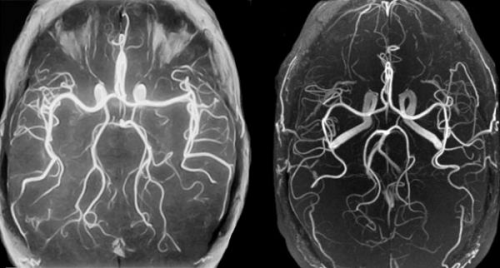

Отличие МРТ от МР-ангиографии

При обращении в больницу, часто можно услышать разные названия процедур. Принципиальных отличий в проведении МРТ и МР-ангиографии нет. Первый вид обследования позволяет изучить нервные ткани головного мозга. А магнитно-резонансная антиография (МРА) выполняет диагностику заболеваний артерий и вен. С помощью венографии – разновидности МРА, можно изучить циркуляцию крови по сосудам, обнаружить нарушения в кровоснабжении мозга, в анатомической структуре сосудов, вывить воспалительные процессы и патологии развития.

Цена МРА сосудов головного мозга зависит от особенностей обследования, так как может выполняться как с контрастом, так и без. При обследовании с контрастом вводиться специальное вещество, которое повышает яркость изображения сосудов.